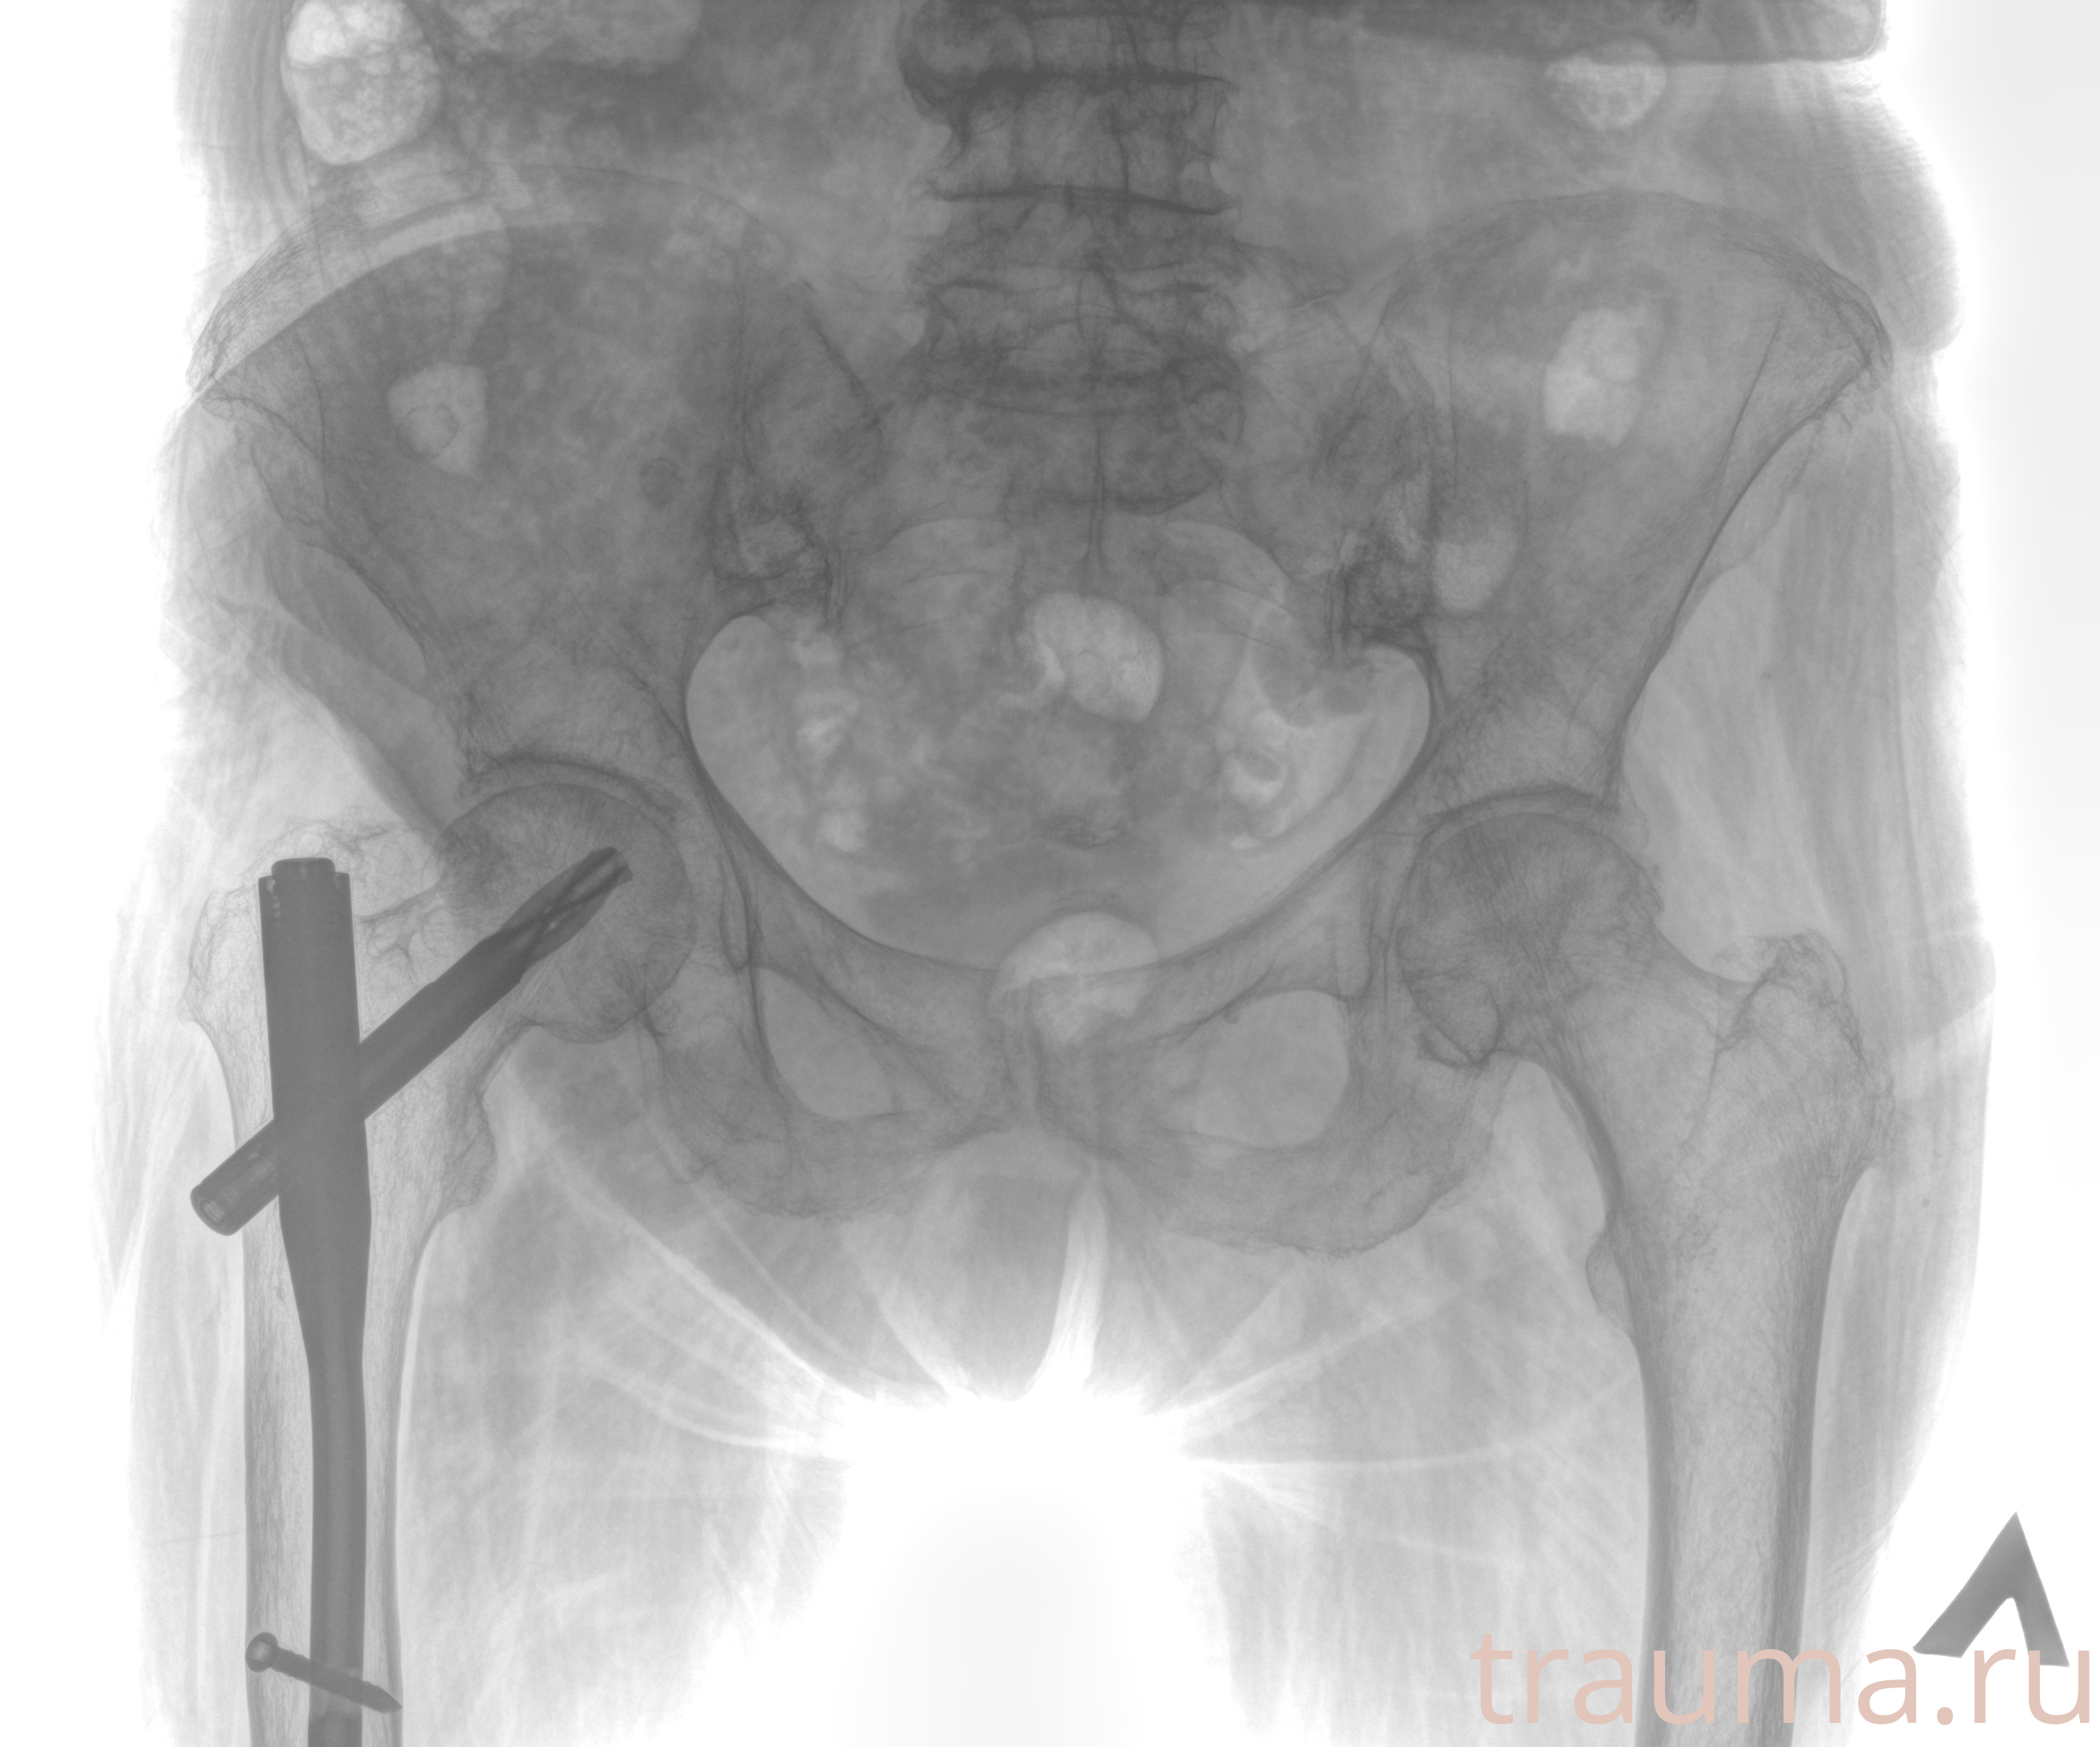

Первая помощь при переломе шейки бедра

Рентген на дому: по вашему адресу приезжает врач-рентгенолог, травматолог-ортопед с мобильным рентгеновским аппаратом, проводит диагностику травмы или заболевания, делает необходимые рентгенограммы, дает рекомендации по дальнейшему лечению. Получить качественные снимки в домашних условиях возможно благодаря уникальной методике, разработанной МосРентген Центром для института  Склифосовского